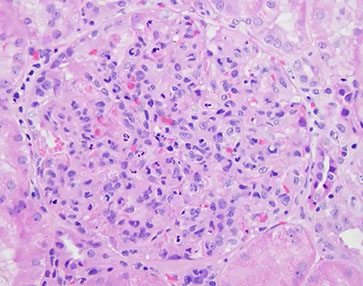

Hemolytic Uremic Syndrome

Endothelial injury results in acute renal failure, caused by systemic microthrombi formation, plt consumption and hemolytic anemia that can result in local necrosis

- MCC ARF in kiddos

- triad: ARF, tbcpenia, MAHA

- can have neuro sx, coagulopathy (similar to TTP)

- usually follows URTI or flu-like illness, can come from fast food hamburgers or spinach / lettuce

Typical HUS manifests as hemorrhagic diarrhea, rapidly progressive renal failure, assoc c O157:H7 cytotoxic E. coli infx

Atypical HUS lacks diarrhea, usually 2/2 complement dysregulation c persistence of complement-mediated microvascular injury

- MC in adults, rarely assoc c ADAMTS13

LM: endothelial injury c edema, sometimes microtrhrombi c fibrinoid necrosis, usually affecting glomeruli; arterial fibrinoid necrosis and thrombosis can be seen, can have glomerular crescents or renal cortical necrosis in severe cases

IF and EM: non-specific; has features of endothelial injury and fibrin staining of microthrombi

Px: kiddos c typical HUS usually recover; atypical HUS (w/o diahhrea) has worse long-term prognosis and can relapse and progress (up to 1/2 mortality)